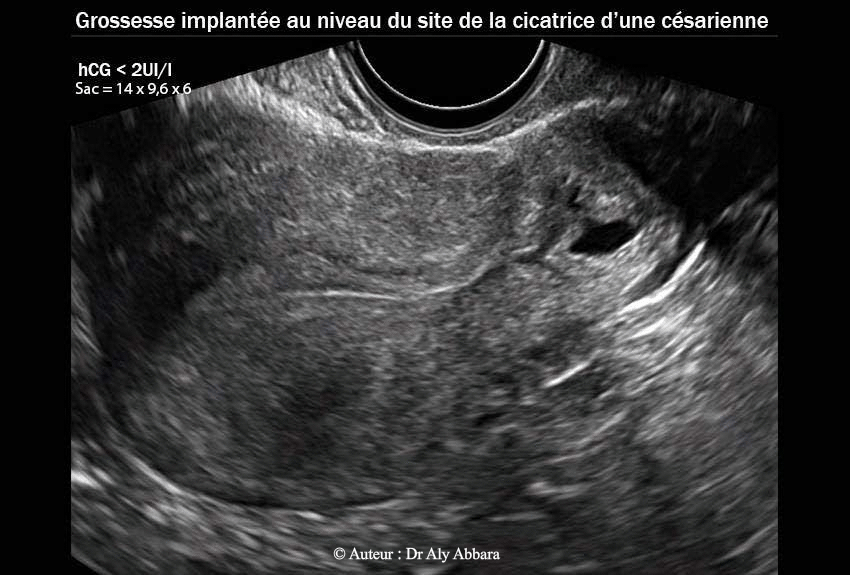

• Images échographiques par voie endovaginale montrant un sac gestationnel d'une grossesse débutante et partiellement intramurale, implantée dans le site de la cicatrice de l'hystérotomie segmentaire transversale d'une ancienne césarienne.

• L'aspect du sac gestationnel au 20e semaine post traitement médical par méthotrexate : il mesure 14 x 9,6 x 6 mm de diamètres (= 0,42 cm3) ; le dosage de β-hCG plasmatique était < 2 UI/l.

21.02.2013 = (J140) = 20 S à < 2 UI/l 14 x 9,6 x 6 mm = 0,42 cm3 J0